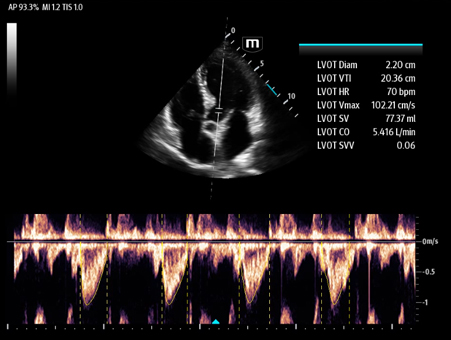

MindrayŌĆśs critical Ultrasound solutions drive improvements in care quality. Integrating advanced hemodynamic Ultrasound features, we can guarantee the highest standard of clinical care. The unique interoperability of Ultrasound and Vital sign data, we can provide comprehensive patient status data, to help inform clinical decisions, enhance clinical efficiency and, ultimately, improve patient outcomes.